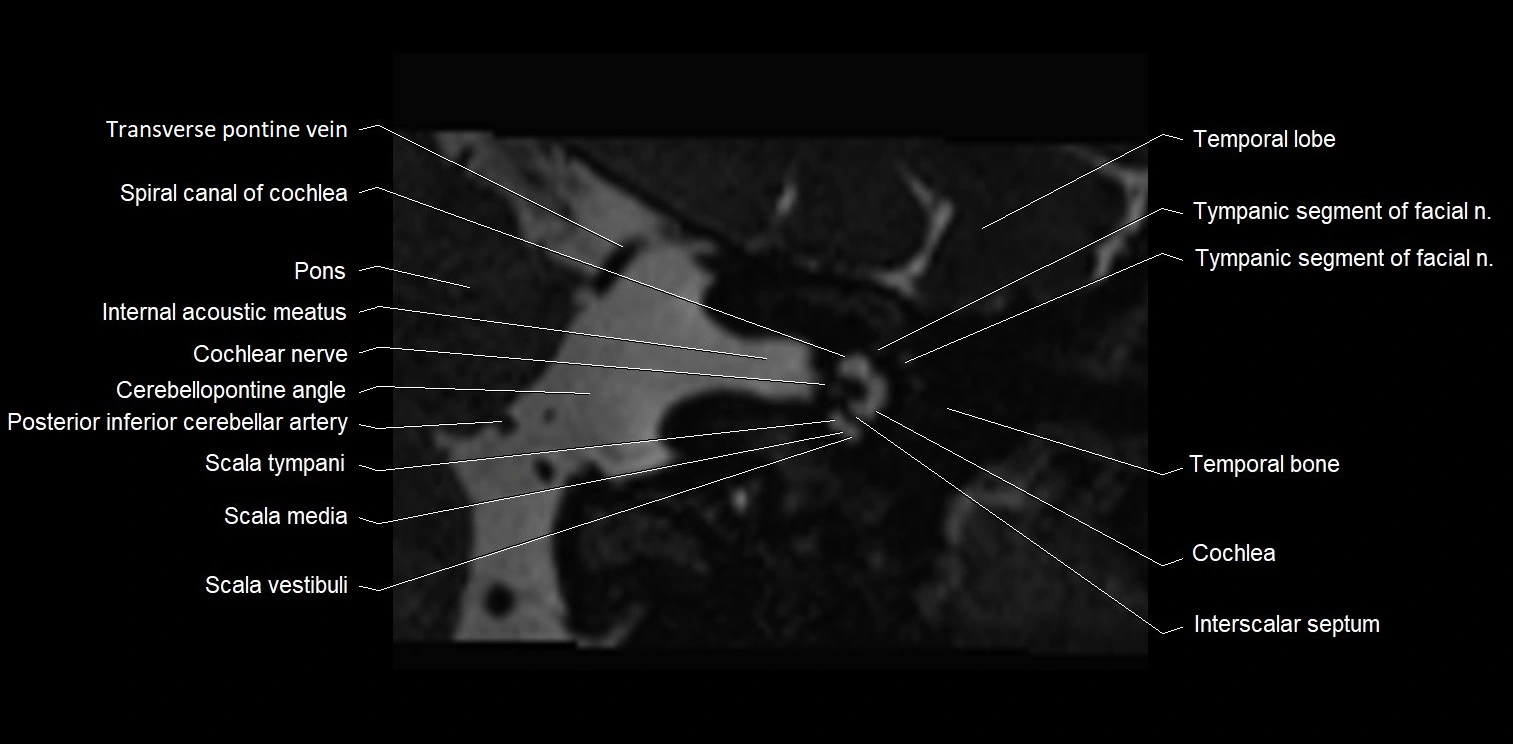

MRI images

image